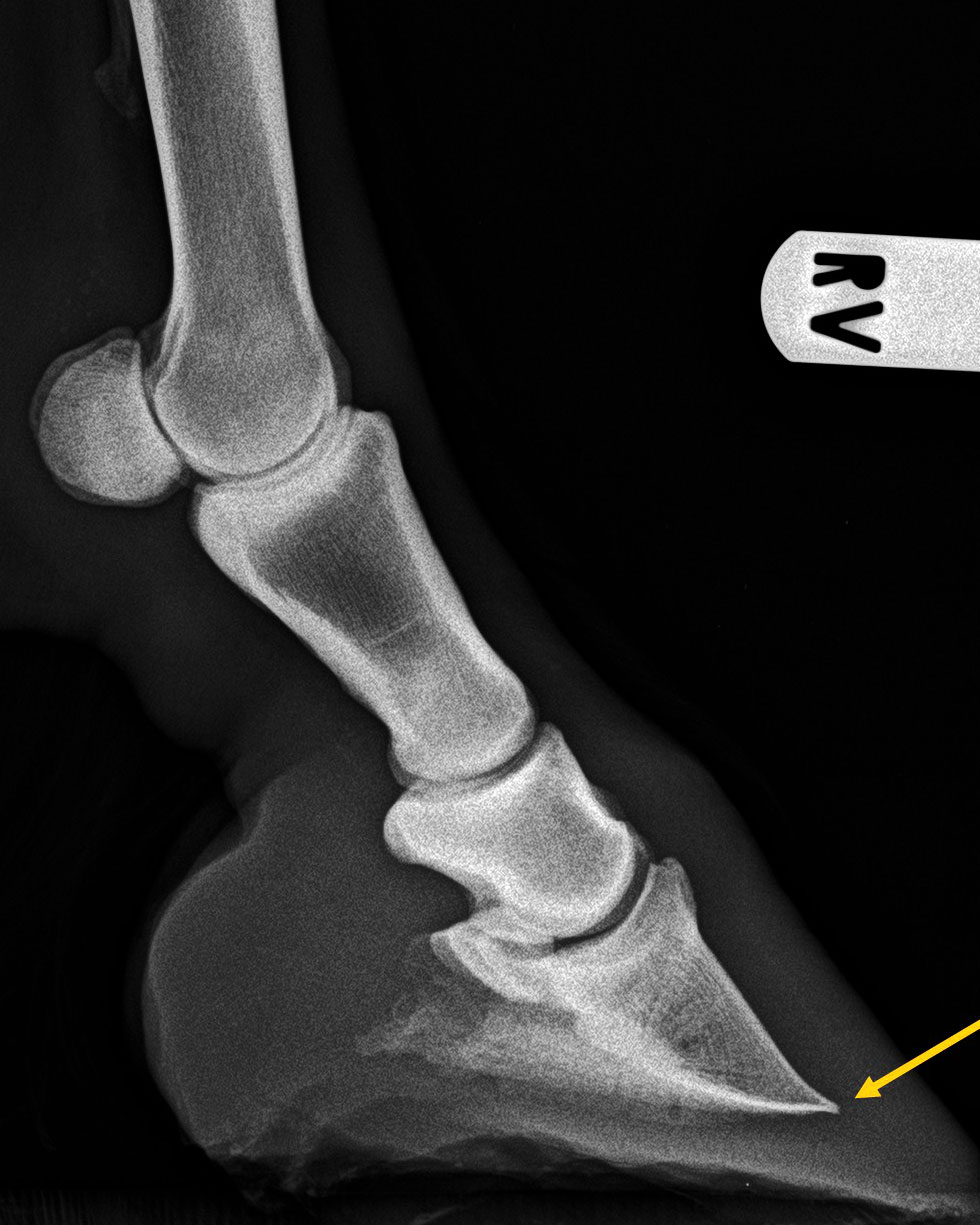

Zehe - 90°-Aufnahme

Verformung der Hufbeinspitze infolge einer Hufrehe wird als Huftkrempenbildung (gelber Pfeil) bezeichnet.